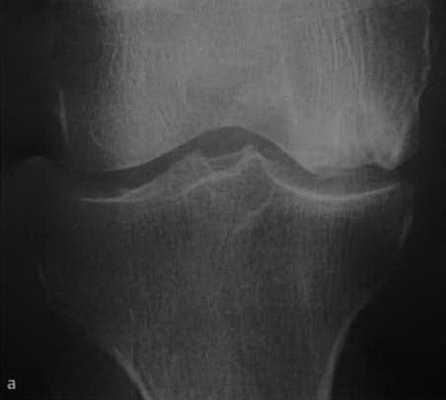

а-d Остеонекроз коленного сустава у женщины 65 лет. Внезапное возникновение болевого синдрома без травмы. Рентгенологическое исследование коленного сустава: (а) в прямой проекции, (b) в боковой проекции. Рентгенопрозрачные участки (стрелка) с окружающим склерозом, дегенеративными изменениями и уплощение суставных поверхностей.

(с), (d) МРТ. Фронтальное протонное плотно-взвешенное изображение с подавлением МР-сигнала от жировой ткани (с) и сагиттальное Т1 -взвешенное (d) изображение. Перифокальный отек и линейные субхондральные участки являются признаками стрессового перелома с дегенеративными изменениями в медиальном мениске.